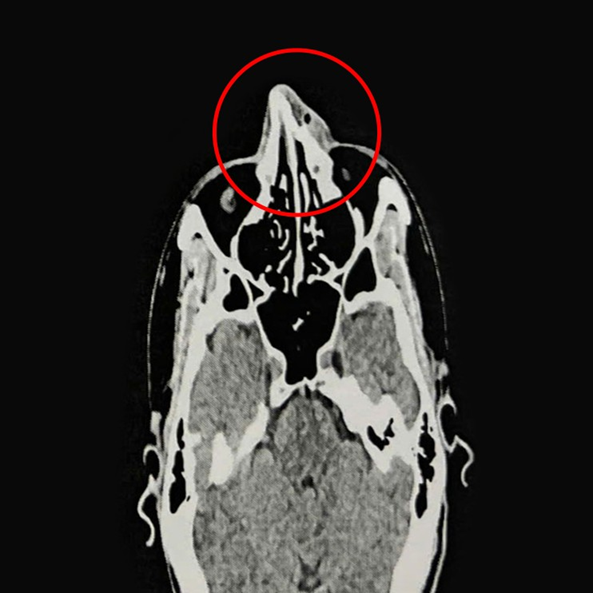

ThS.BS.CKI Nguyễn Trung Nguyên, Trung tâm Tai Mũi Họng, Bệnh viện Đa khoa Tâm Anh TP.HCM, cho biết kết quả nội soi và chụp CT 128 lát cắt ghi nhận xương mũi của anh Phi bị gãy ở vị trí tháp mũi, phù nề tụ khí mô mềm vùng mũi, lệch vách ngăn mũi, viêm mũi xuất tiết. Anh Phi được chỉ định phẫu thuật nâng xương mũi, chỉnh hình vách ngăn mũi.